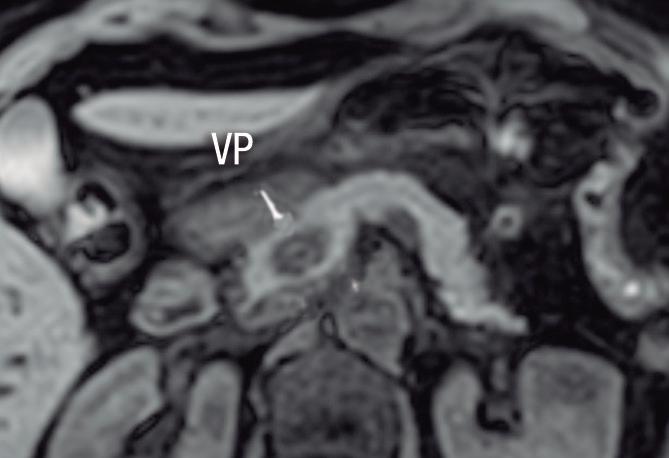

Páncreas Circumportal

El páncreas engloba a la vena mesentérica superior o vena porta, en lugar de rodear al duodeno como sucede en el páncreas anular (Figura 14). Tiene una prevalencia de hasta 2,5% según algunas series, por ende, no es tan infrecuente encontrarlo en estudios por imágenes. Se

A B

postula que su origen está relacionado con una anomalía en la rotación y fusión del brote ventral con el dorsal. Es una condición asintomática, pero cobra relevancia reconocerla e informarla en pacientes que serán sometidos a cirugía del páncreas, con el fin de reducir complicaciones, particularmente la fístula pancreática.25, 26

A) Resonancia magnética, secuencia T2, plano coronal. Se observa un páncreas “truncado”, con ausencia de tejido glandular a la izquierda del cuello (flecha), coincidente con una agenesia parcial del brote embriológico dorsal. La cabeza de flecha nos muestra a la porción cefálica prominente, redondeada. B) Resonancia magnética, secuencia T1 con contraste, plano axial. Flecha: Limite de finalización de la glándula, a la izquierda de la arteria mesentérica superior. Cabeza de flecha: Porción cefálica prominente, redondeada. C) Resonancia magnética, secuencia T1 con contraste, plano axial, corte más caudal. Las flechas muestran hipertrofia relativa del proceso uncinado (brote ventral), el cual llega a ubicarse por detrás de los vasos mesentéricos superiores, incluso superando el plano de la arteria. AMS: arteria mesentérica superior.

A) Resonancia magnética, secuencia T1 sin contraste, plano axial. Tejido pancreático con típica señal hiperintensa en secuencia de ponderación tisular T1 (cabezas de flecha), rodeando a la vena porta (VP). B) Resonancia magnética, secuencia T1 con contraste, fase portal, plano axial. VP: vena porta, VE: vena esplénica, AMS: arteria mesentérica superior.